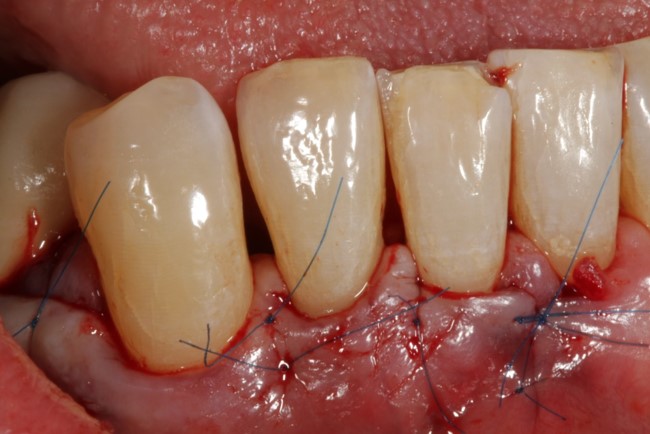

07/08 - Flap repositioning and suturing.

Non-contained intrabony defect treated using Straumann® Emdogain® and a synthetic bone grafting material - Prof. Dr. Dr. A. Kasaj